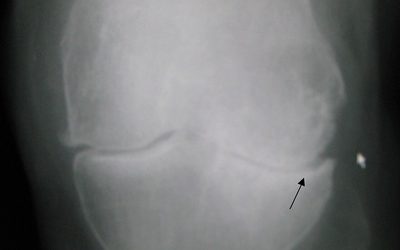

Artralgia y osteoartritis: manejo natural del dolor crónico